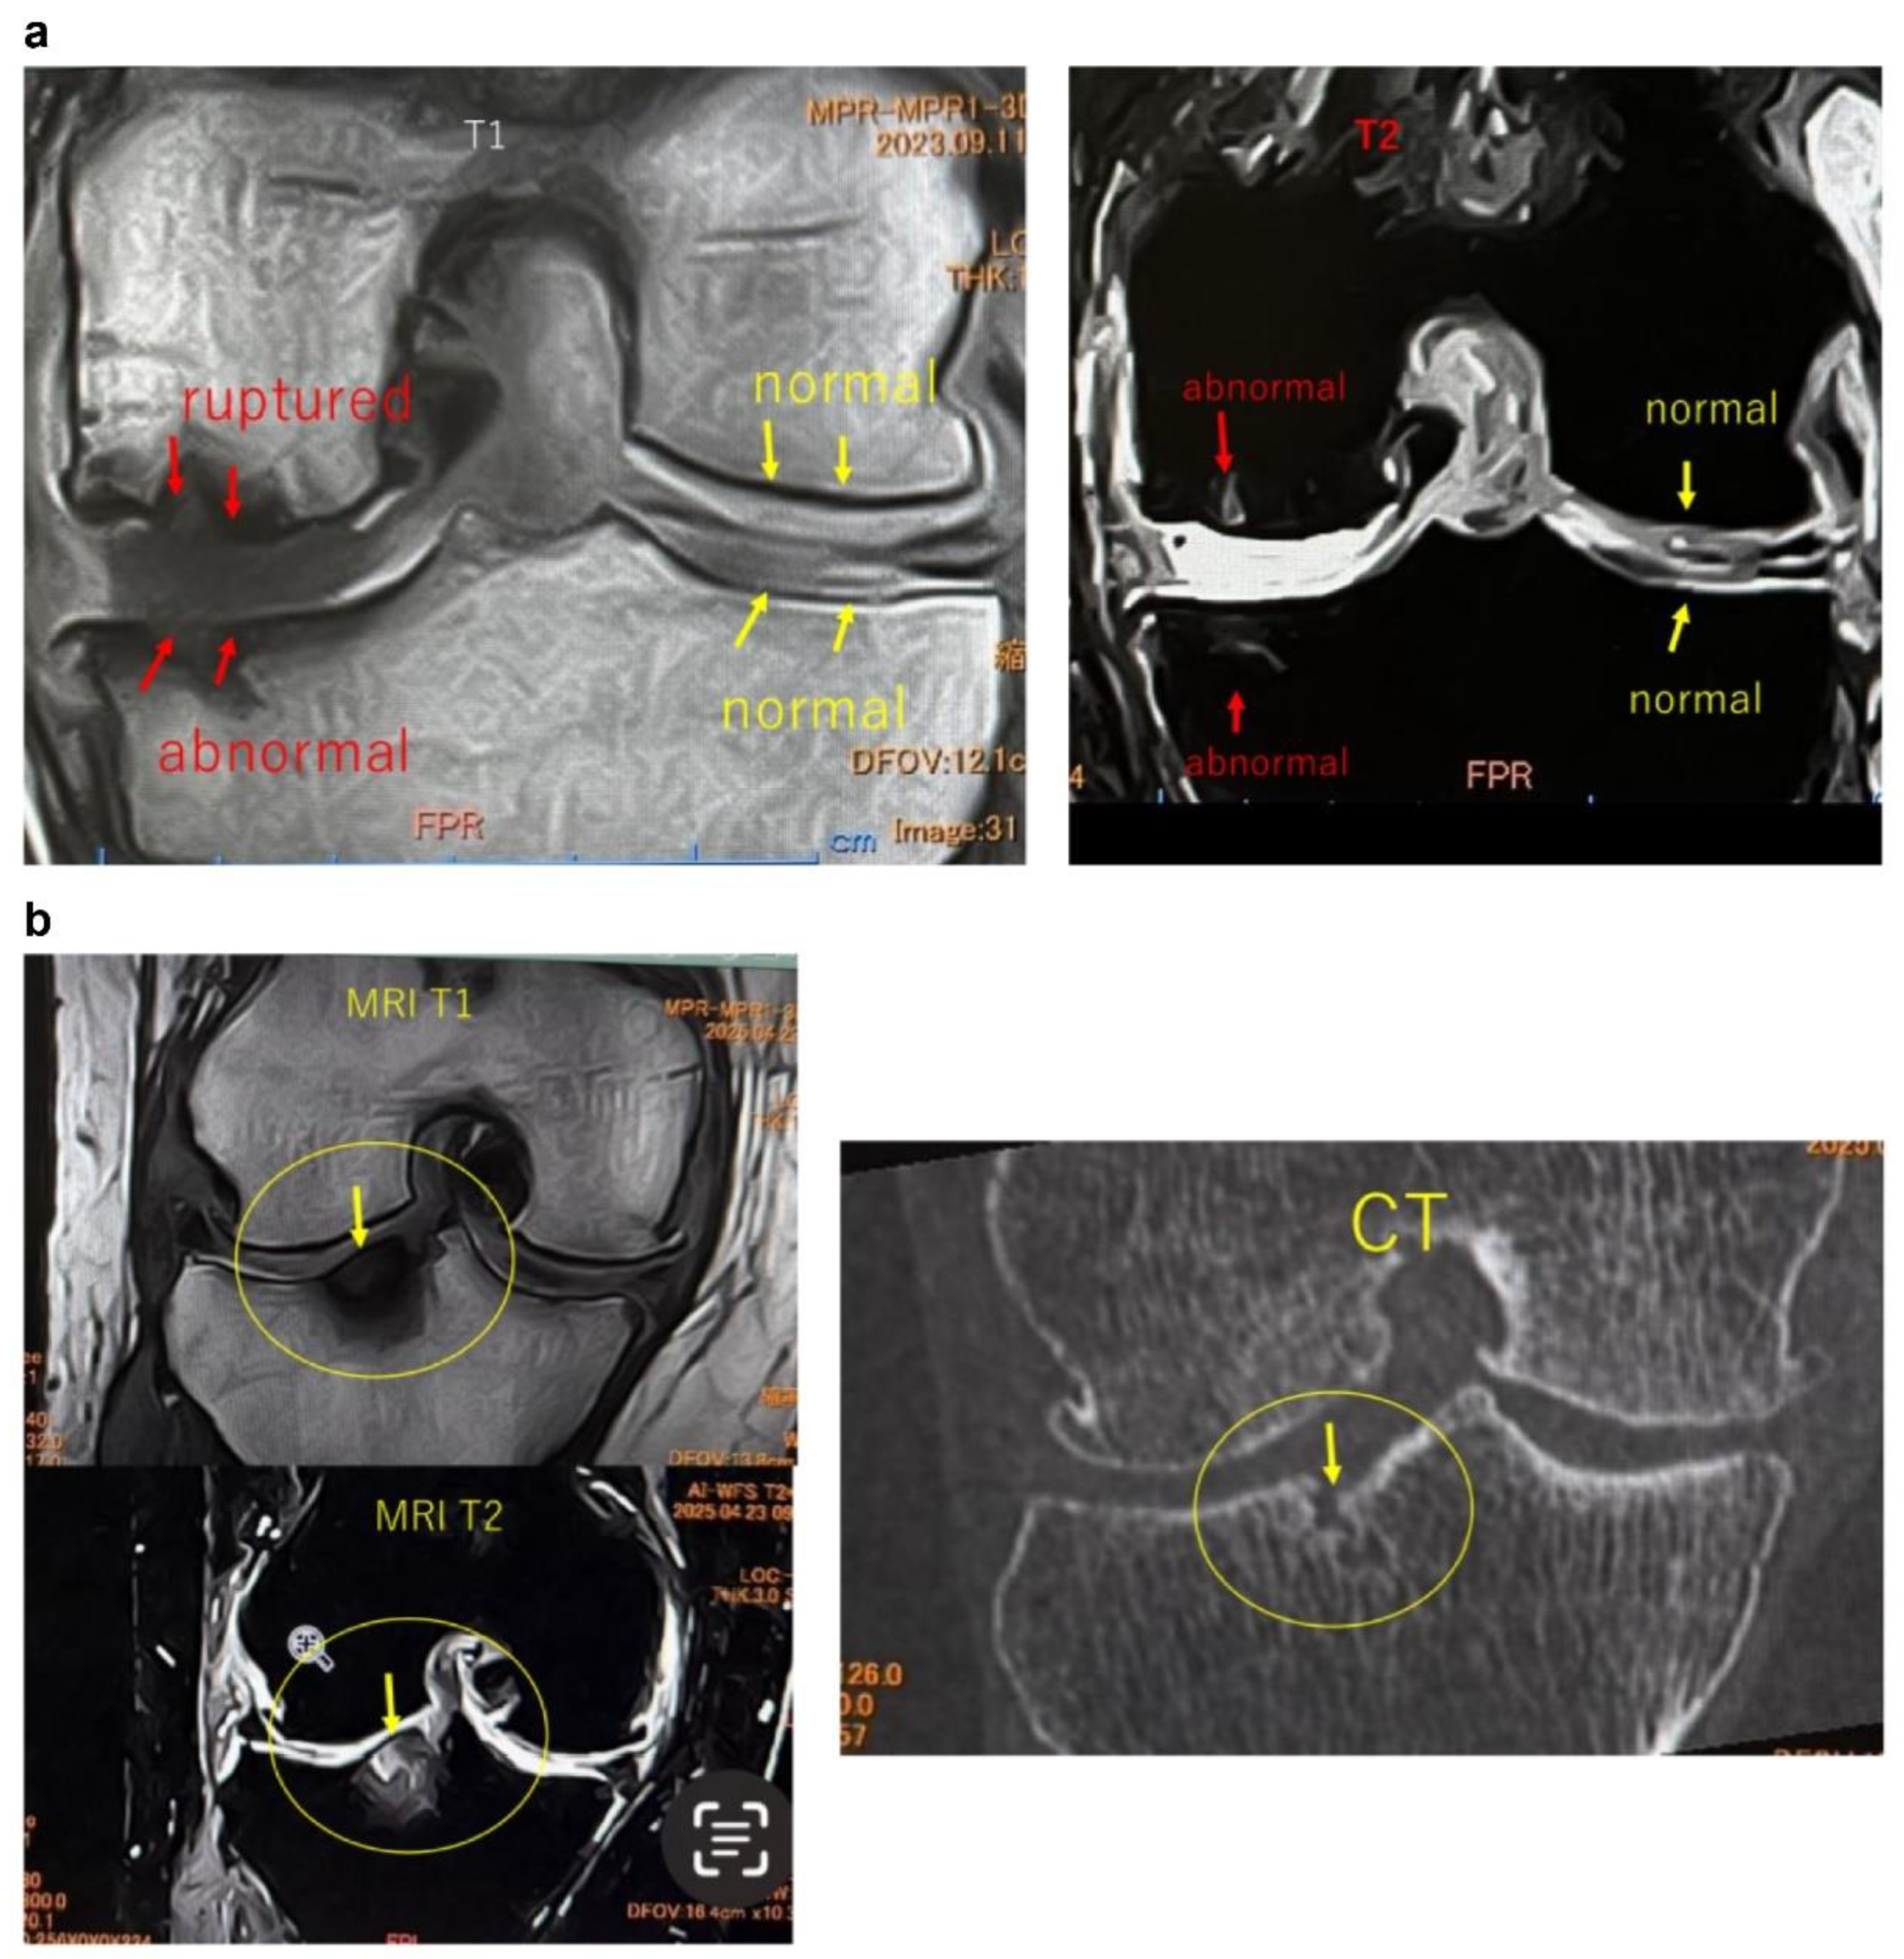

Figure 2.

Imaging findings of normal and ruptured subchondral bone plate (SBP-tear). (a) Magnetic resonance imaging (MRI) findings of normal and ruptured subchondral bone plate (SBP-tear). Coronal sections of the knee joint are shown on T1-weighted (left) and T2-weighted (right) images. The SBP appears as a low-signal band, similar to cortical bone. The normal SBP, indicated by yellow arrows, demonstrates preserved continuity and a smooth contour. In contrast, the areas marked with red arrows show apparent disruption and irregularity of the SBP. Notably, on T2-weighted images, the presence of joint fluid signal extending into the marrow cavity suggests SBP disruption. (b) Evaluation of SBP disruption using MRI and computed tomography (CT). The left upper panel shows a T1-weighted MRI image, the left lower panel shows a T2-weighted MRI image, and the right panel presents a coronal CT image. In the MRI images, the areas indicated by yellow arrows demonstrate a clear loss of SBP continuity (SBP-tear). On T2-weighted images, the disruption is more distinctly visualized due to the contrast with joint fluid signals. When the detection of SBP tear is challenging on MRI, CT imaging can provide clearer visualization of the cortical tear in the SBP.